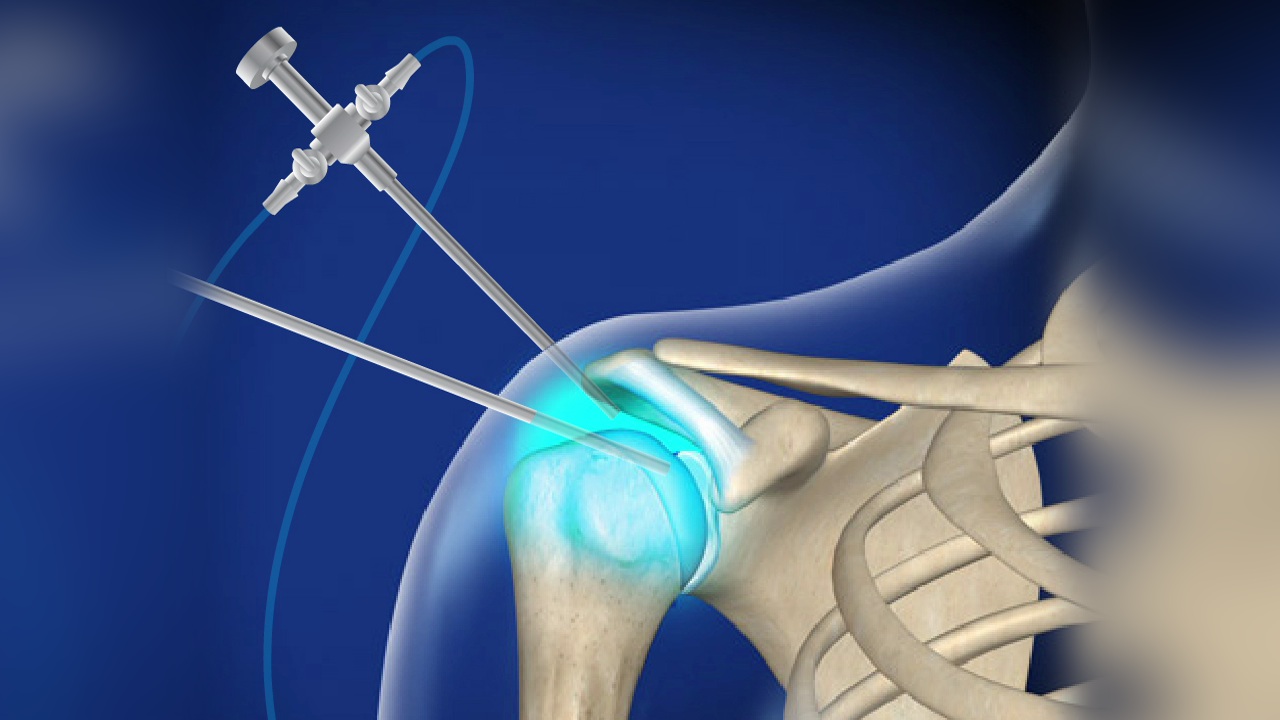

How is Hip Fracture Surgery Performed?

Hip fracture surgery is performed to realign the broken bones to their proper position before the fracture occurred. This is done through one of the following methods:

- Open Reduction: In this procedure, a surgical incision is made in the hip skin, allowing the surgeon to directly manipulate the bones’ alignment.

- Closed Reduction: In this approach, the doctor modifies the bones’ position without making a surgical incision. The procedure typically lasts about two to three hours, and in some complex cases, it may require more time. The patient is put under general anesthesia and may spend a few hours in the recovery room after the operation.

Whether the doctor chooses an open reduction or closed reduction, they will work to stabilize the bones to prevent them from moving during the healing period. This is achieved using internal or external fixation with specific medical devices such as wires, pins, screws, or plates. These devices are usually removed after 6 to 12 months following the surgery.